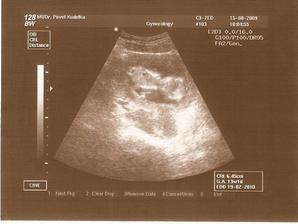

15.10. - tak dneska jsme se dozvěděli, že to opravdu bude Barborka, máme velikou radost!!!Velký UTZ proběhl naprosto v pořádku, tak hlavně aby to tak pokračovalo i dál.